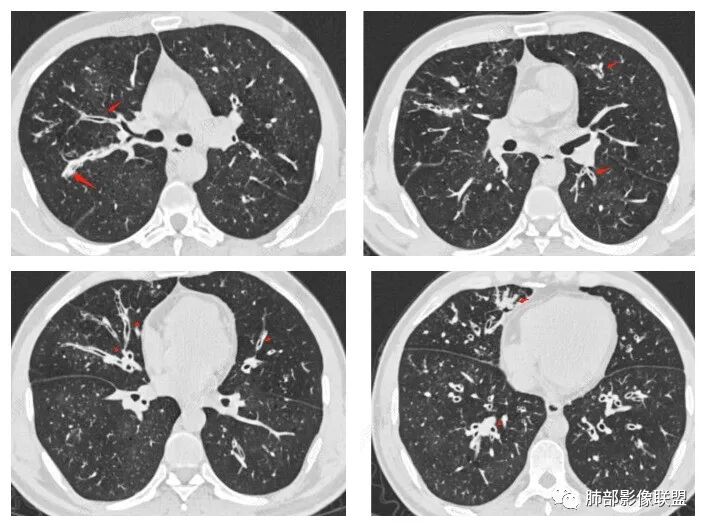

晨读:最关键的有三点:1、临床表现及病史:35岁,男性,慢性刺激性咳嗽2月,吸烟史17年,没有糖尿病和其他免疫缺陷病史。这儿应该隐瞒了关键的吸入环节,存在大量曲霉孢子的工作环境没给。2、第一次影像改变:广泛的支扩,支气管壁增厚,多发的树芽,部分区域已经伴有支气管周围的渗出,少量实变。3、20多天后复查的影像,原有支扩,支气管壁增厚基础上的大量渗出,实变,伴结节,胸膜下累及。

上述表现最符合的就是气道侵袭性曲霉菌病(IPA),刺激性咳嗽2月支持最初的气道改变:广泛的支扩,支气管壁增厚(支气管粘膜充血,水肿,以及伪膜形成)树芽征,而后期大量支气管周围渗出,实变,伴结节,胸膜下累及,也符合IPA的进展表现,病史中未提及是否有胸闷,气喘等(估计后期有,没提供而已)。

2.胸部CT:两肺广泛的支扩,支气管壁增厚,多发的树芽影,部分伴有支气管周围的渗出,少量实变。不足一月复查,原有支扩、支气管壁增厚基础上伴有大量渗出,实变,结节,胸膜下累及。

3.综合分析:首先病灶沿支气管分布,呈树芽征及实变影,相应支气管壁广泛增厚,其次病变范围比较广泛,几乎累及所有叶段,这种表现常高度提示气道播散,经过对症抗感染治疗20多天后,胸部CT影像明显进展。符合IPA的进展表现。

1、气管、主支气管、叶段支气管支气管壁弥漫增厚,壁厚度较均匀,内壁不光滑,以一侧为主

2、病灶沿气管外壁侵犯纵隔,引起纵隔脂肪间隙增宽,密度增高,部分可见少量积气

3、段以下支气管堵塞,远端合并阻塞性不张、树芽征、斑片状实变影;

4、支气管腔内粘液栓。